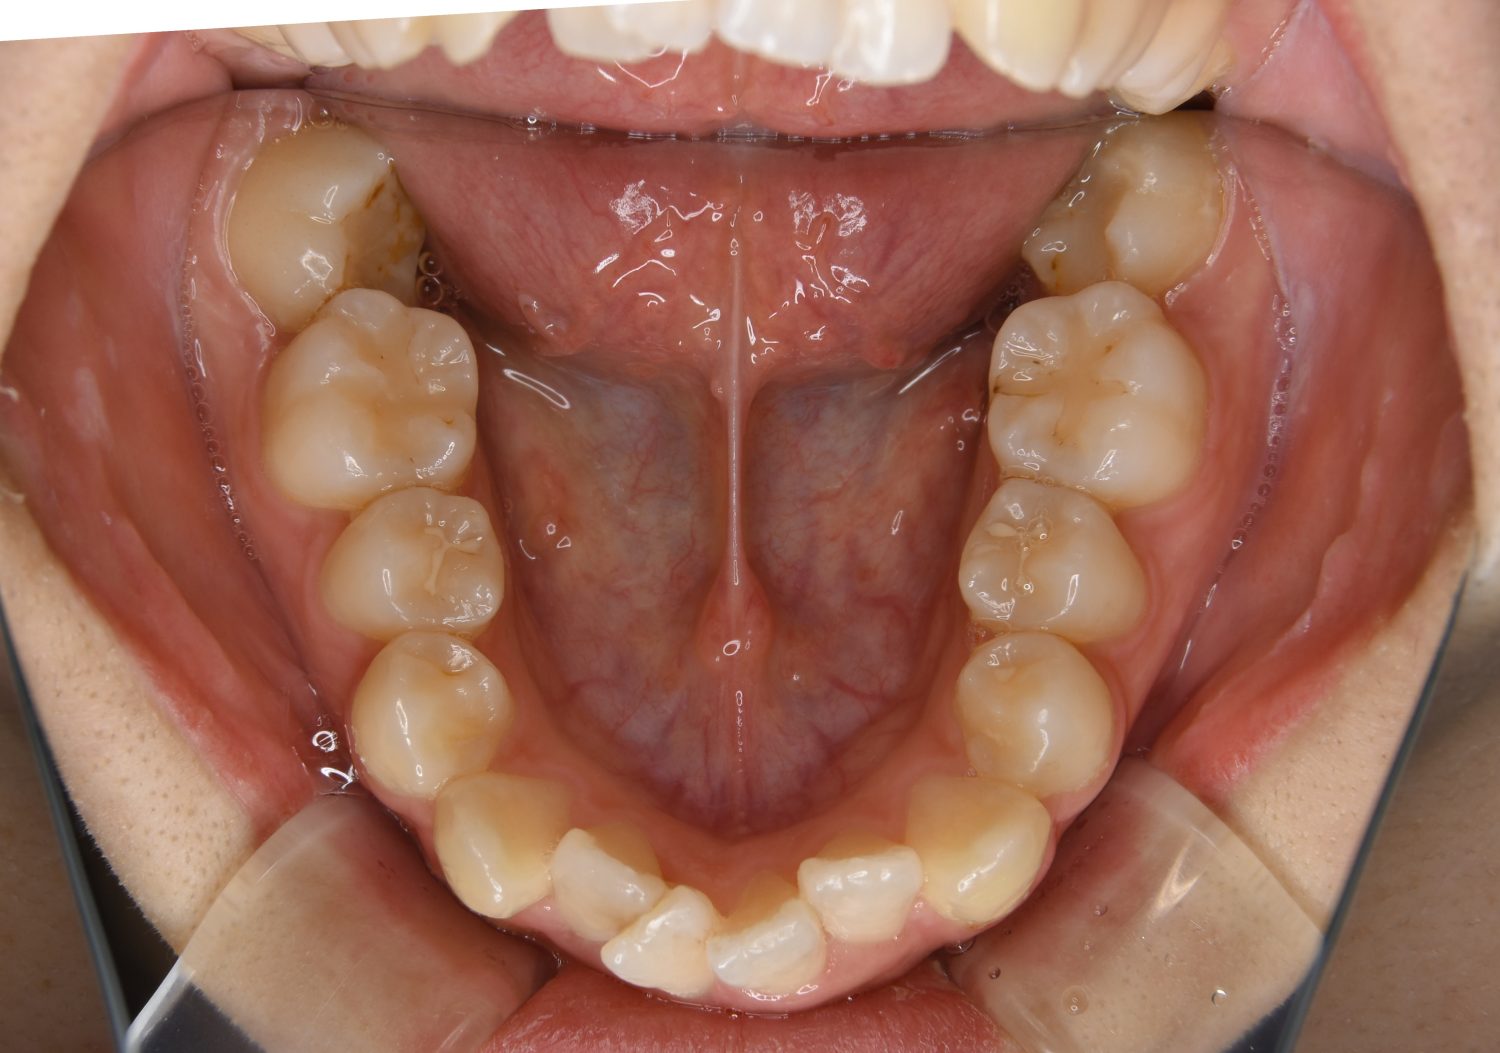

叢生の症例紹介②

Before

After

主訴

歯の凸凹を治したい。

治療内容

アライナー(インビザライン)にて非抜歯で治療を行いました。

治療費

1,150,000 円(税込)

治療期間

26ヶ月

通院回数

14回

想定されたリスク

※歯根吸収、歯肉退縮、歯髄壊死、顎関節症状

※アライナー(インビザライン)は日本の薬機法未承認の矯正装置であり、医薬品副作用被害救済制度の対象外となる場合があります。

丸山和宏先生

ピーススマイル矯正歯科

上下前歯部に叢生(凸凹)が認められる状態でした。歯列の遠心移動を行うことで機能面および審美面が改善されました。